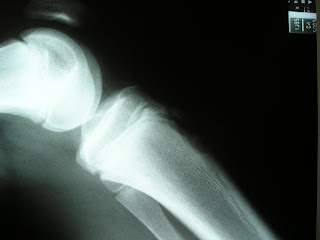

¿Qué otras pruebas complementarias pedirías? ¿Cuál sería el tratamiento de elección? ¿Realizarías radiografía de control?

Caso clínico 51

Caso clínico 50

Caso clínico 49